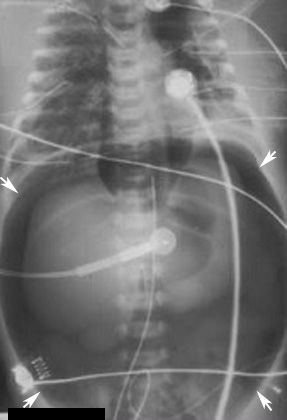

Football sign

The football sign refers to a large oval radiolucency in the shape of an American football, which is seen on supine abdominal X-ray films.[1] The football sign is most frequently seen in infants with spontaneous or iatrogenic gastric perforation causing pneumoperitoneum.